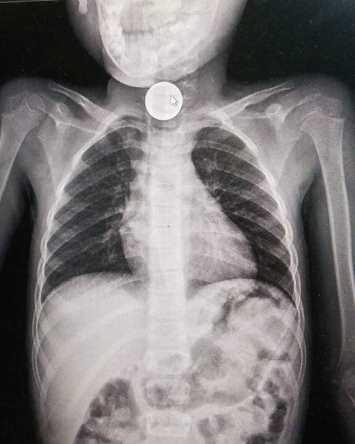

إزالة أجسام غريبة من جهاز هضمي لطفل بالأردن

2021-06-13